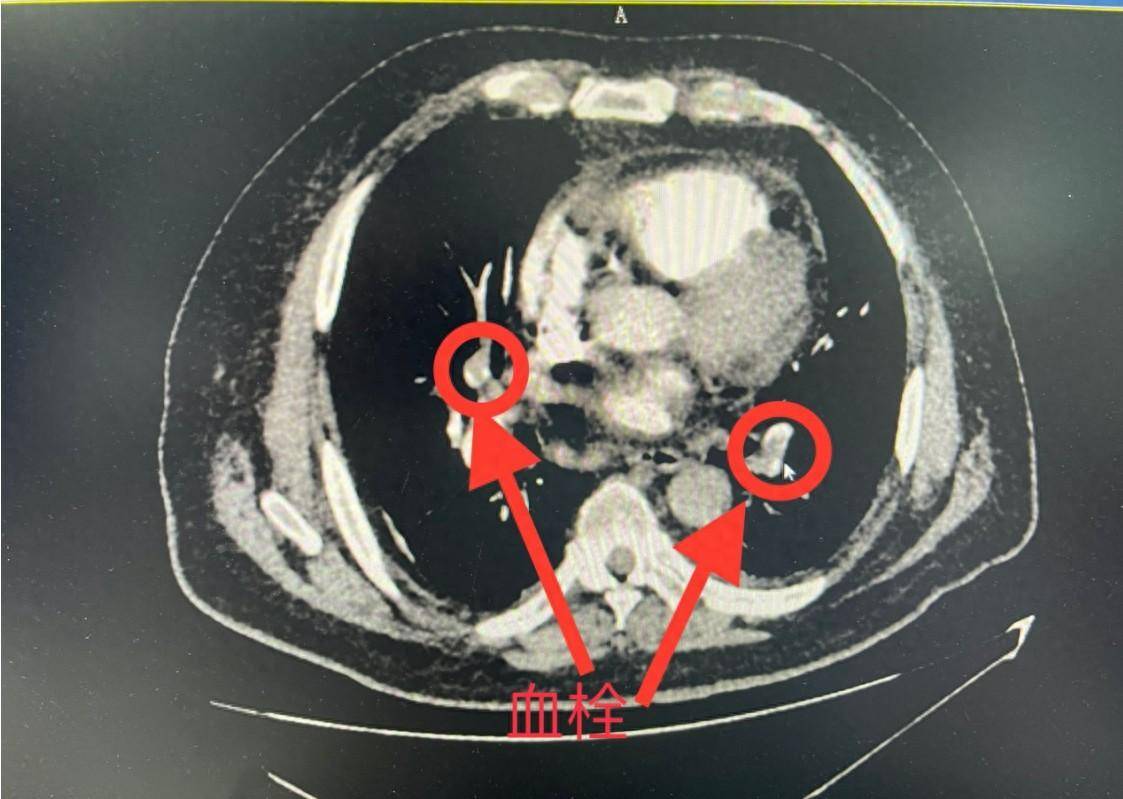

急诊查肺动脉ct血管造影(cta),示两侧肺动脉栓塞;d-二聚体>3.

事不宜迟,许嗲嗲经绿色通道被快速送入放射影像科行肺动脉cta检查.